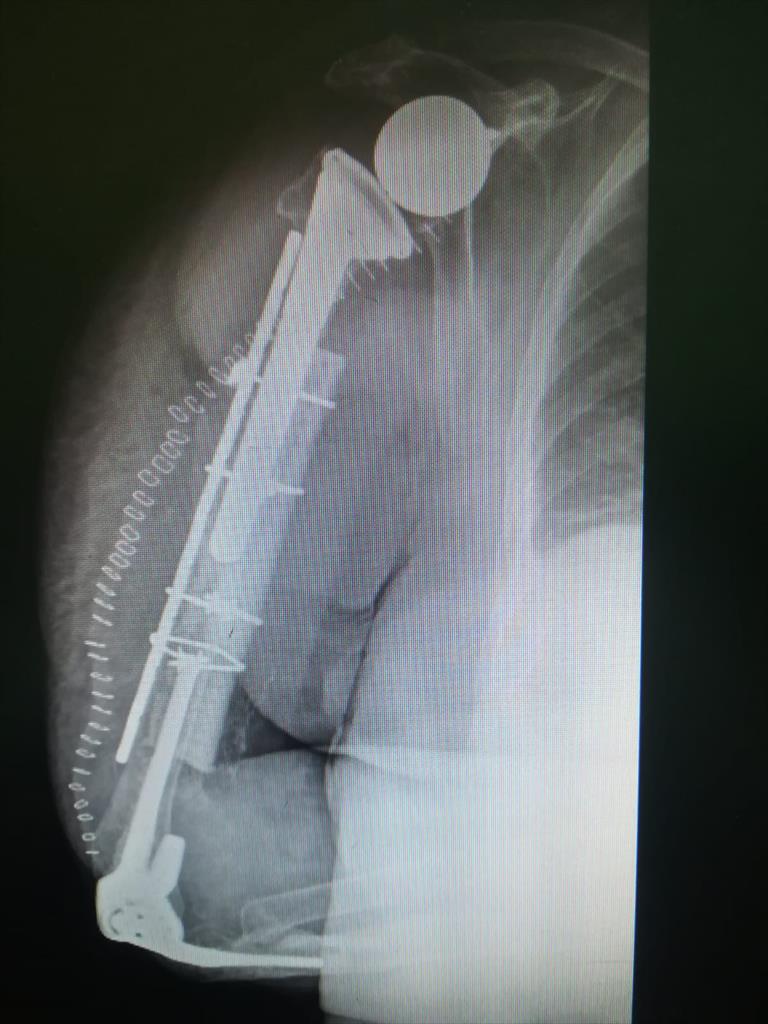

È stato eseguito nei giorni scorsi presso la struttura di Ortopedia e Traumatologia dell’Ospedale di Perugia, diretta dal professor Auro Caraffa, un intervento chirurgico innovativo di ricostruzione omerale per il trattamento di una rarissima lesione di una frattura interprotesica, tra spalla e gomito, riportata da una signora perugina di 75 anni dimessa oggi. Nella letteratura scientifica internazionale sono riportati pochissimi casi di questo tipo di lesione che sono stati trattati con tecniche sperimentali diverse da quella eseguita, per la prima volta al mondo, dai chirurghi ortopedici perugini. Si tratta di un intervento innovativo con caratteristiche di unicità sia per il tipo di lesione riportata, frattura tra due protesi di spalla e di gomito entrambe cementate, sia per il trattamento effettuato mediante l’utilizzo di tecniche e di materiali più avanzati a disposizione nello scenario internazionale. L’operazione, eseguita dal chirurgo ortopedico dottor Lorenzo Maria Di Giacomo, e’ consistita nella stabilizzazione e ricostruzione delle fratture interprotesiche mediante l’utilizzo di un innesto biologico osteogenico e di una stecca (graft) corticale di origine animale.  Come spiega il dottor Di Giacomo: “Si tratta di fattori di crescita osteogenici di origine biologica e di osso corticale di origine equina reso compatibile per l'innesto”.